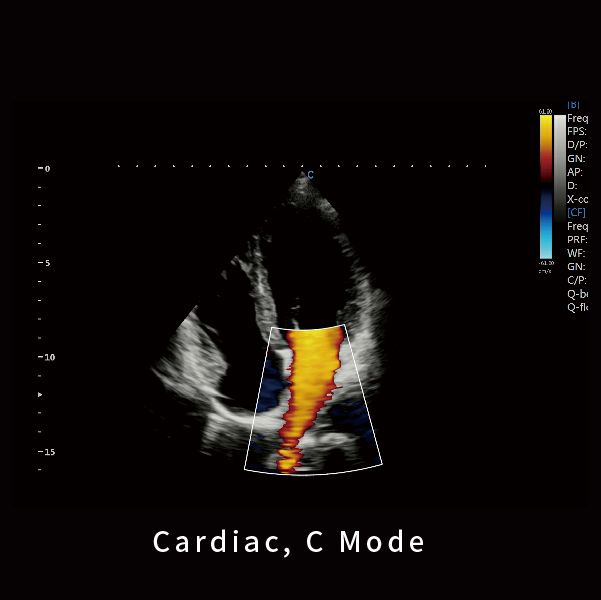

心脏,C模式